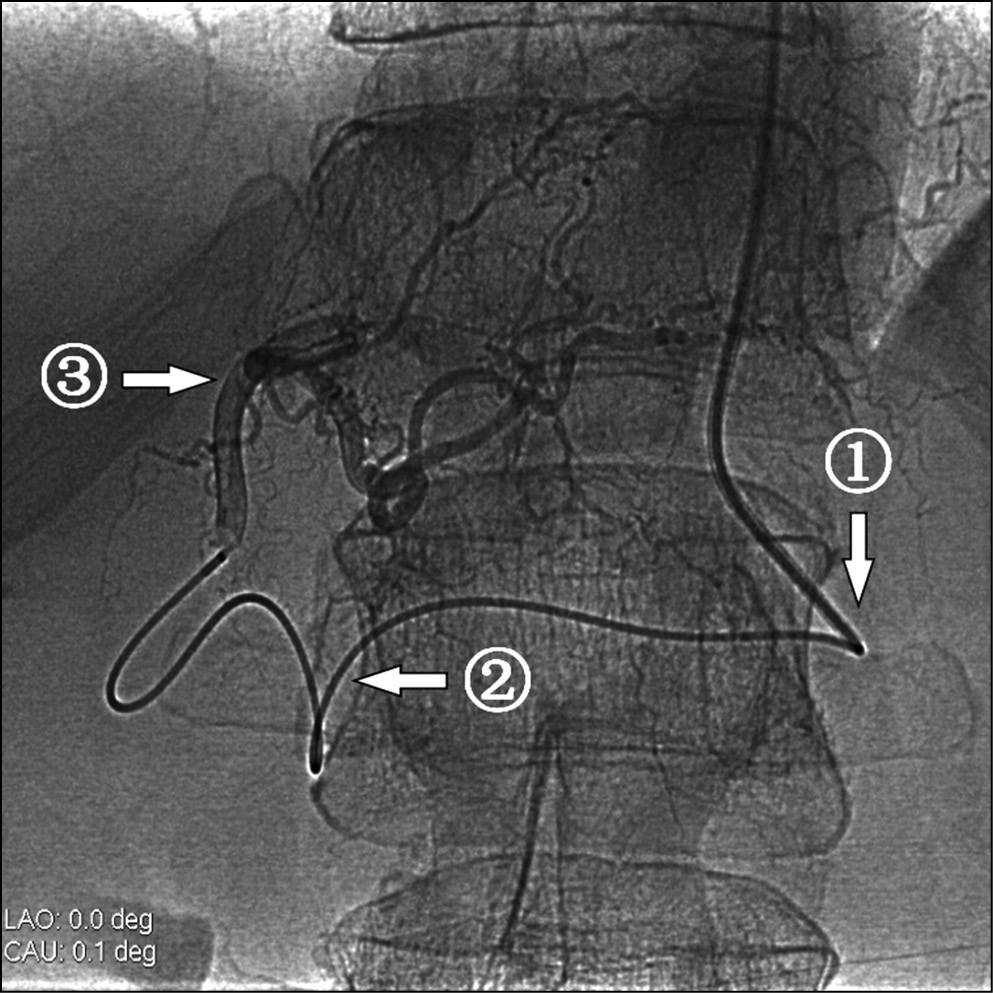

Рис. 2. Селективная катетеризация микрокатетером сегментарных ветвей правой печеночной артерии при окклюзии чревного ствола

Примечание. 1 — ангиографический катетер 5F в устье верхней брыжеечной артерии, 2 — микрокатетер, проходящий из верхней брыжеечной артерии через a. pancreatiсoduodenalisinferior и ретроградно через а. pancreatiсoduodenalissuperior и a. gastroduodenalis в правую печеночную артерию, 3 — кончик микрокатетера в сегментарной ветви правой печеночной артерии.